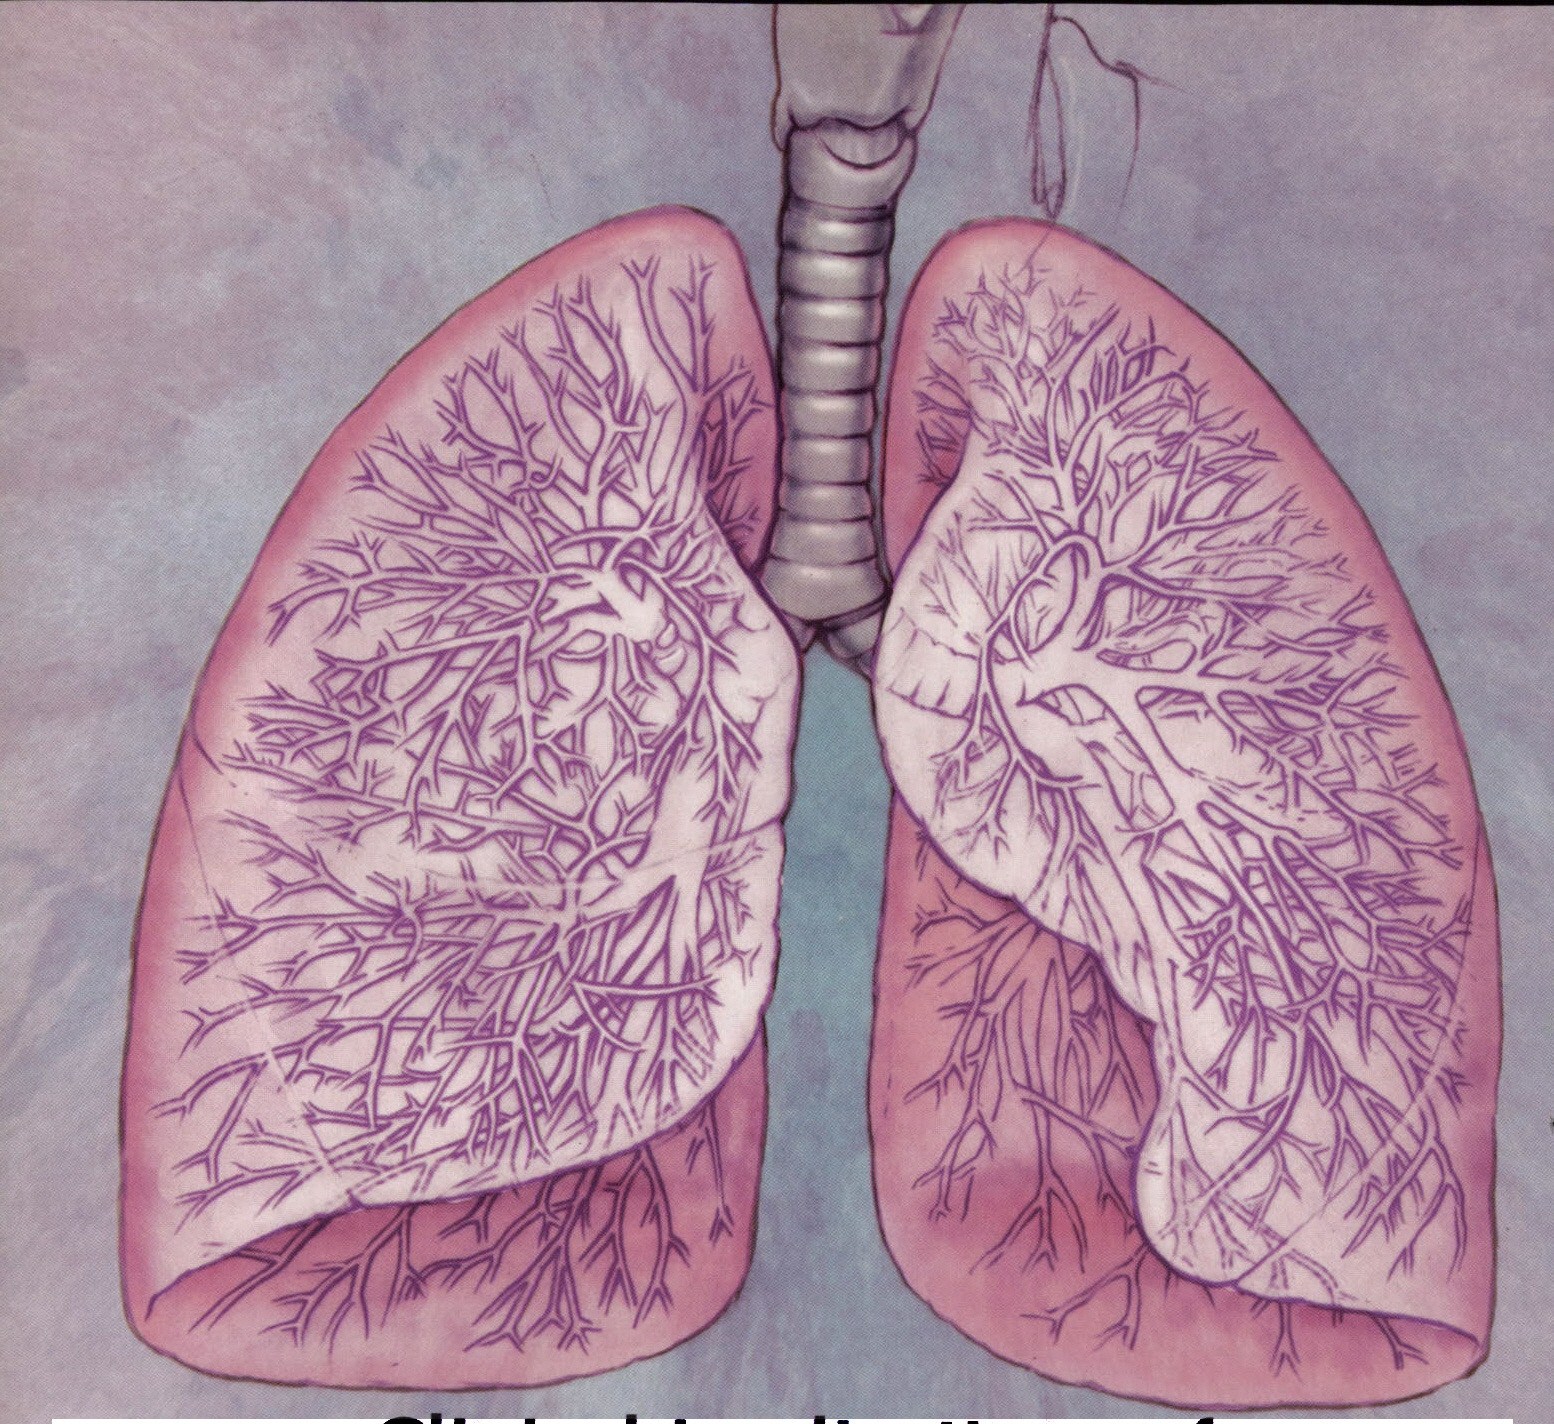

Фотографии, демонстрирующие обнаруженное усиление легочного рисунка

Раздел: Фотодневник открытий